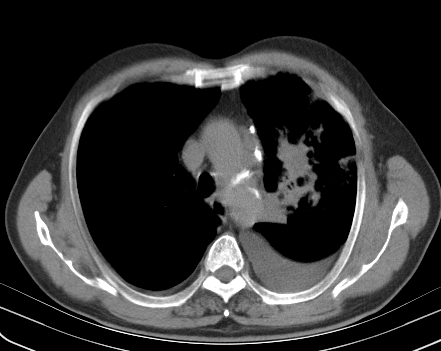

以下是引用老爱克斯新网客在2008-7-31 6:30:00的发言:[br]左肺上叶大片状病灶,左肺上叶支气管狭窄呈鼠尾状,左肺门增大,纵隔内见肿大淋巴结,左侧胸腔积液,余肺清晰。左肺中心型肺癌淋巴结转移,

以下是引用zjb在2008-7-31 6:32:00的发言:[br]左侧中心性肺癌 阻塞性肺炎 肺不张 胸腔积液 建议气管镜

以下是引用zjzjr在2008-7-31 8:45:00的发言:[br]考虑左侧中心性肺癌伴阻塞性肺炎,左肺上叶肺不张,纵隔淋巴结转移;左侧胸腔积液。建议行纤支镜检查。

以下是引用sdzyy在2008-7-31 8:47:00的发言:[br]病灶较治疗前有所进展,胸水增多, 左侧中心性肺癌 并 阻塞性肺炎 肺不张 胸腔积液 可能性大; 建议气管镜检查。 [br] [br]